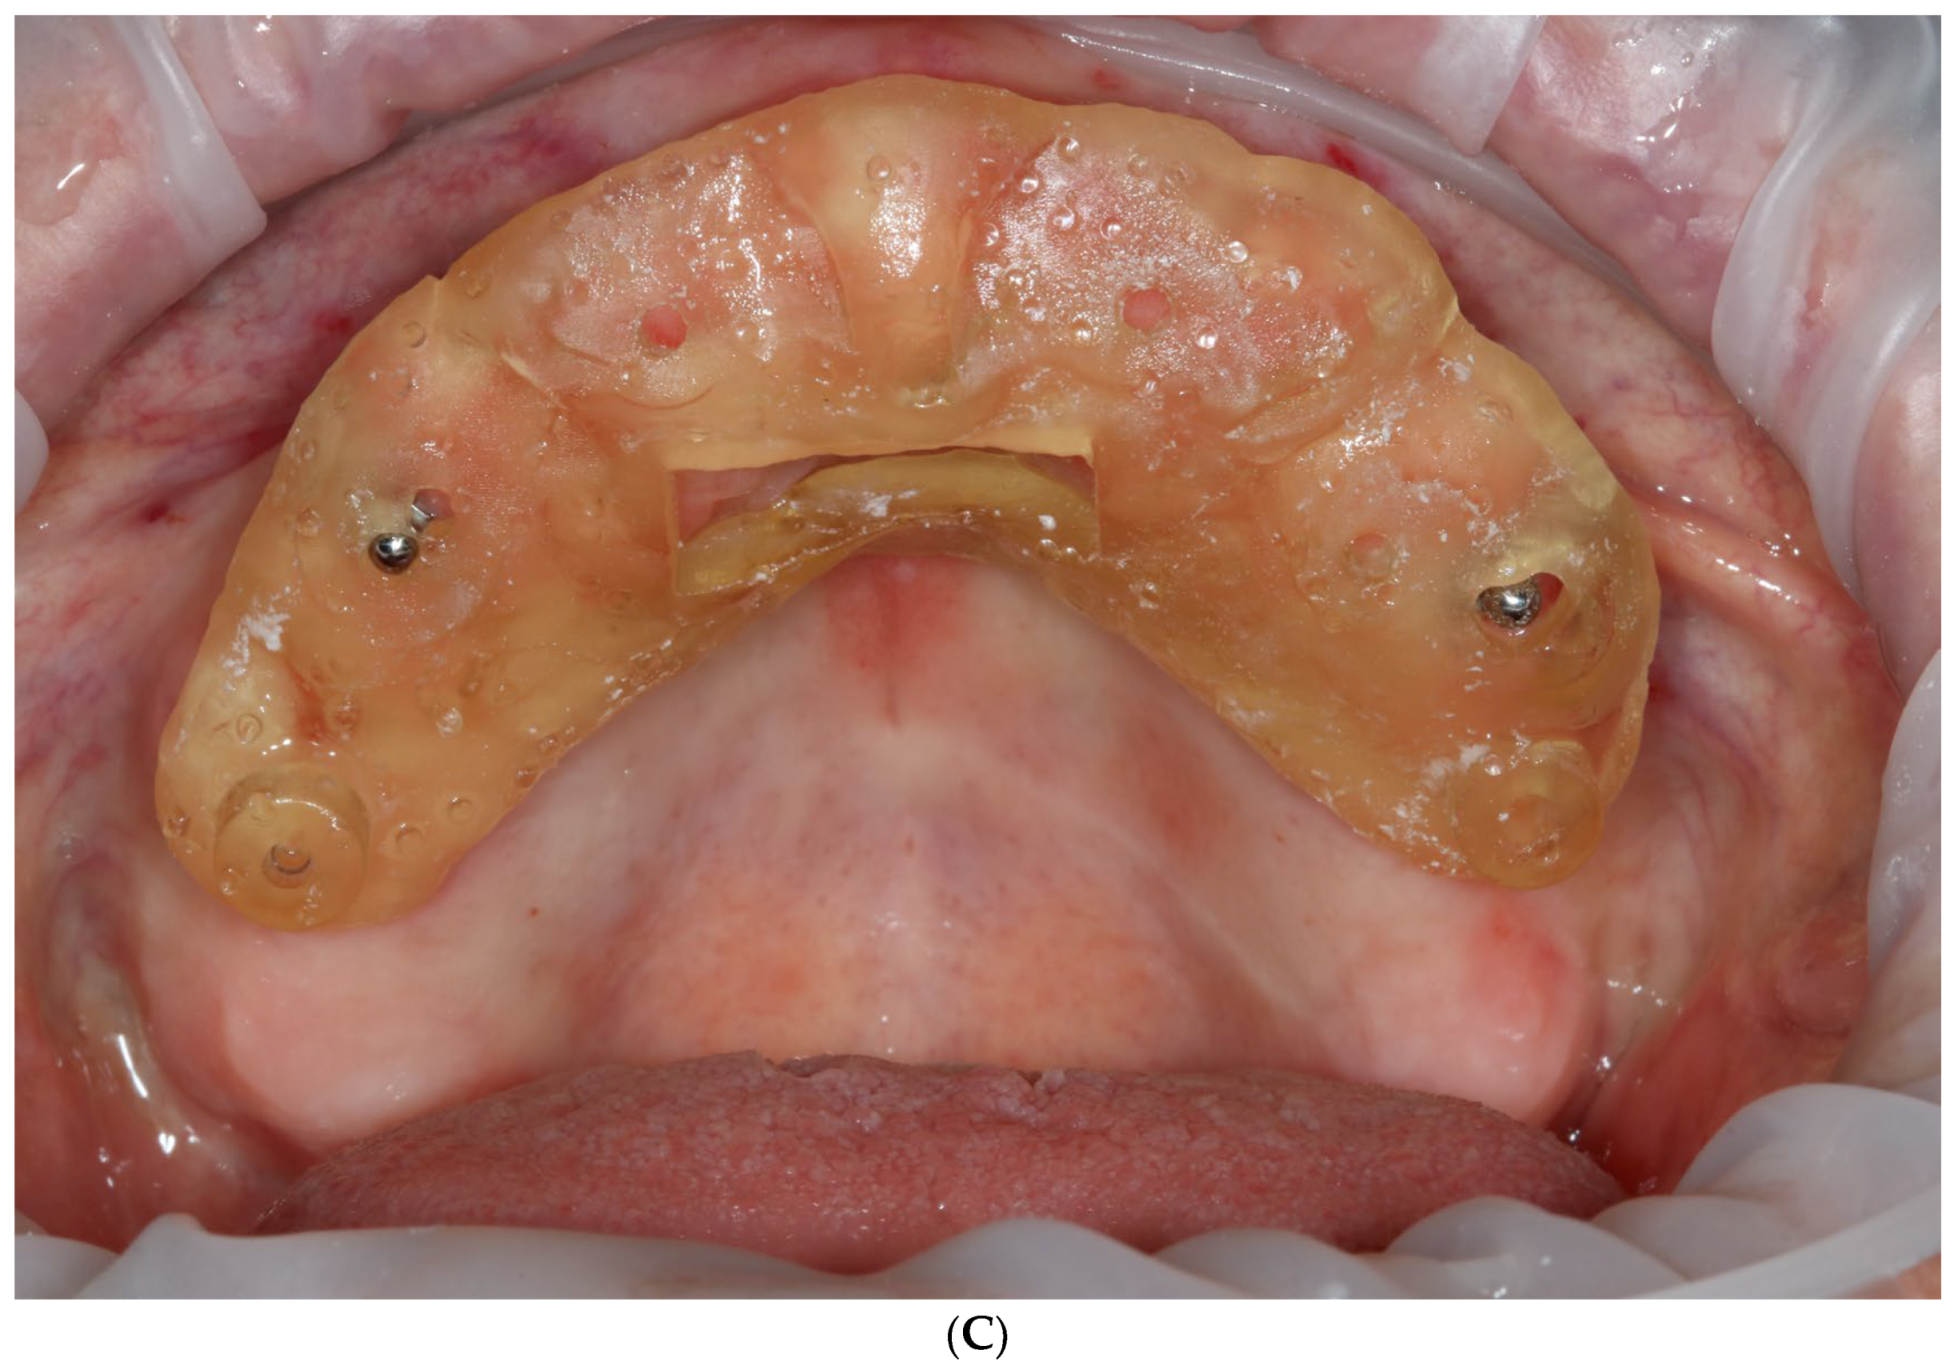

2.2.1. Stage I

- Extraction of remaining teeth, immediate temporary implant placement, and removable denture delivery.

- The extraction of remaining teeth and immediately give removable 3D printed dentures inserted on the temporary implants to the patient;